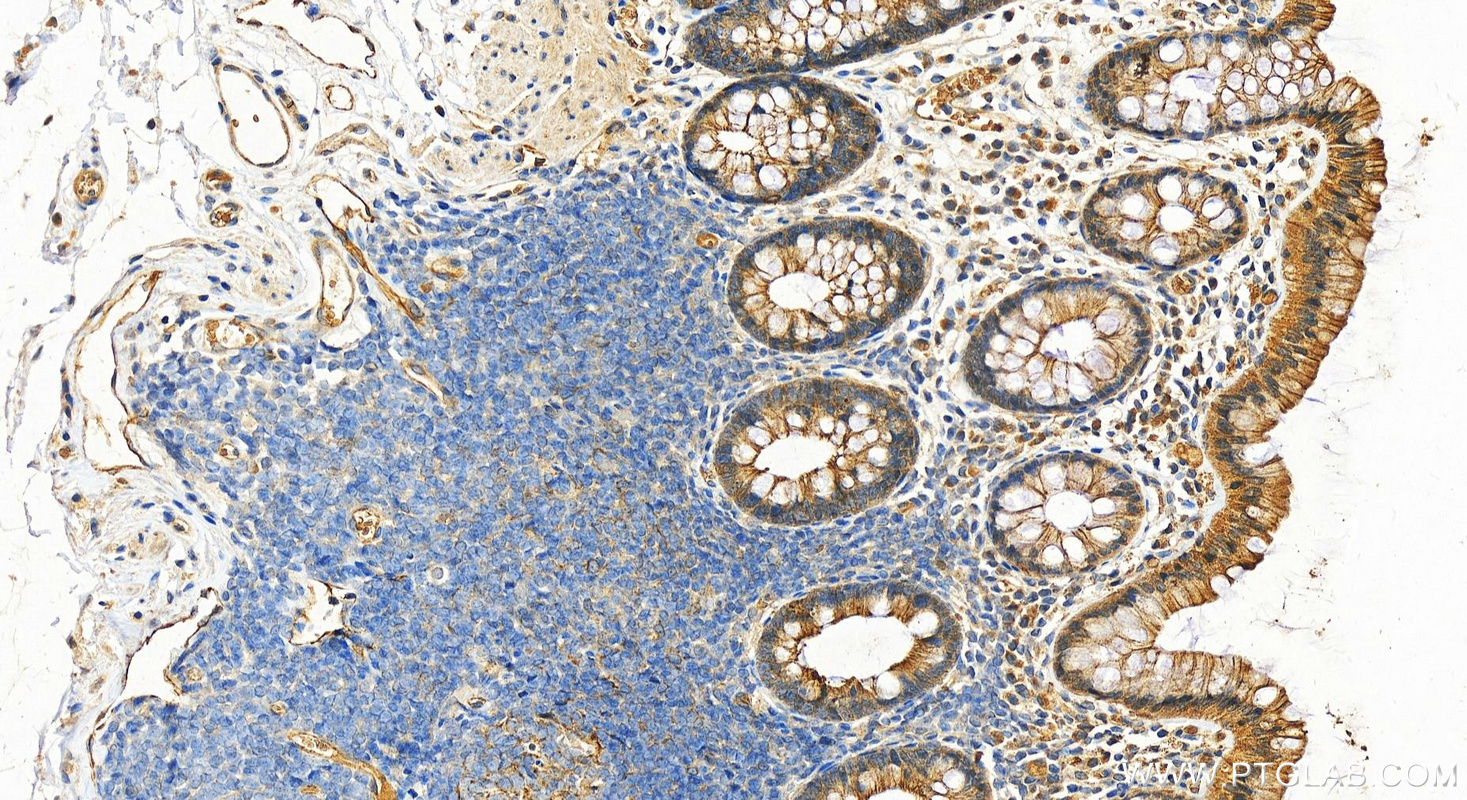

| Positive IHC detected in | rat heart tissue, human normal colon, human bowen disease, mouse heart tissue Note: suggested antigen retrieval with TE buffer pH 9.0; (*) Alternatively, antigen retrieval may be performed with citrate buffer pH 6.0 |

| Immunohistochemistry (IHC) | IHC : 1:2500-1:10000 |